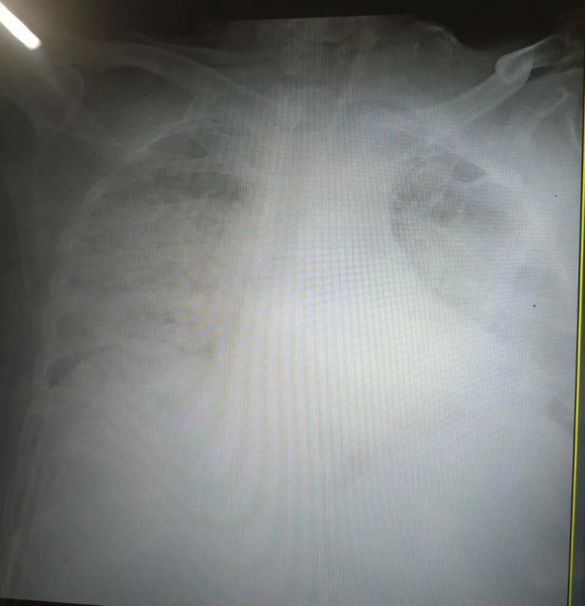

У Львові медики показали, який вигляд мають легені, уражені коронавірусом. Органи на світлині перетворилися на суцільну світлу пляму.

«Це одні з найстрашніших легенів, які я бачила в житті», – сказала мені щойно очільниця реанімації клінічної лікарні швидкої медичної допомоги Львова», – написала Ірина.

Нагадаємо, що патологоанатом розповів, як коронавірус змінює легені. Лікар говорить, що вони більше нагадують печінку.